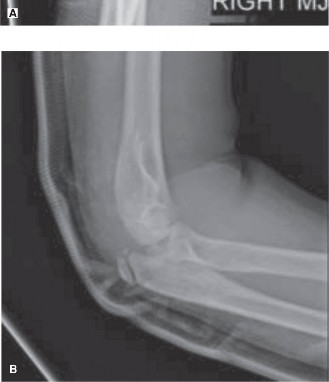

Standard anteroposterior (AP), lateral, and oblique views of the wrist were obtained. These showed no evidence of acute fracture or dislocation of the distal radius, carpal bones, or metacarpals. Specifically, there were no avulsion fractures noted from the trapezium, scaphoid, or second metacarpal base, which are common insertion points for the FCR or its slips. The distal radial physis (growth plate) appeared open and anatomically aligned, without signs of Salter-Harris injury. The absence of bony injury on plain radiographs, while reassuring for skeletal integrity, shifted the focus more definitively towards soft tissue pathology.

Figure 1: Representative plain radiographs (AP and lateral views) of a pediatric wrist. In this patient, radiographs were unremarkable for acute fracture or dislocation.